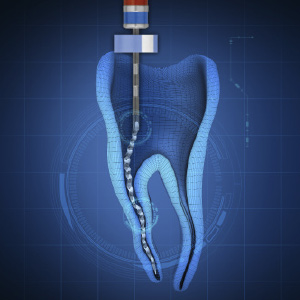

Steps to Endodontic Success for the General Practice

Stephen Christy, DMD

Wednesday, September 29, 2021

This Inside Dentistry eBook offers a continuing education (CE) article that serves as a step-by-step guide for general dentists to achieve endodontic success in their practices. Download to earn 2 FREE CEU now!